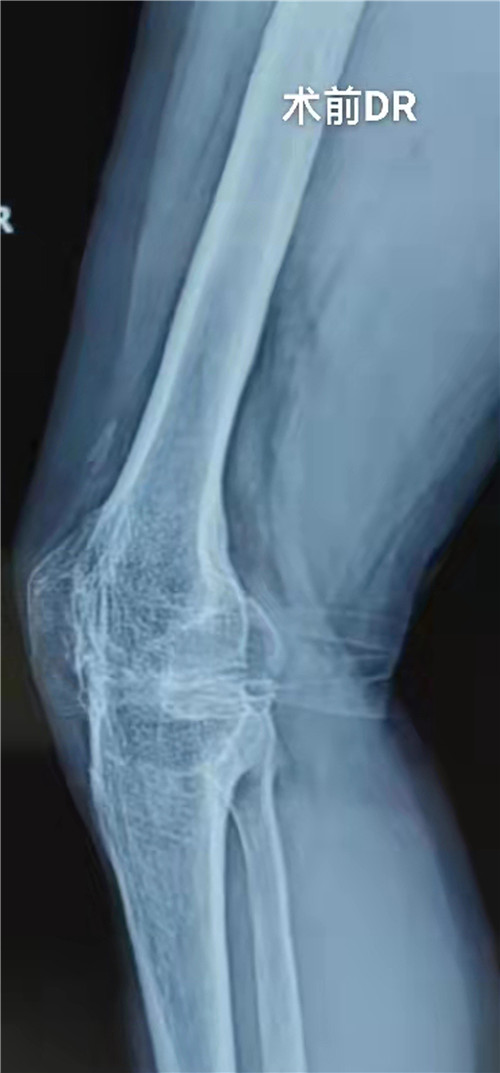

患者约15年前右膝关节受伤后致髌骨骨折,因当地医疗条件受限予以保守治疗后畸形愈合,膝关节畸形、功能障碍,后曾在外地就诊,实行了2次右膝关节软组织松解术,无明显改善。15年来症状逐步加重,现右膝关节呈屈膝15°强直畸形,饱受痛苦,患者为改善生活质量来市三院就诊,入院后经查体及完善相关检查,明确诊断为:右膝创伤性关节炎右膝关节融合;右髌股关节融合。